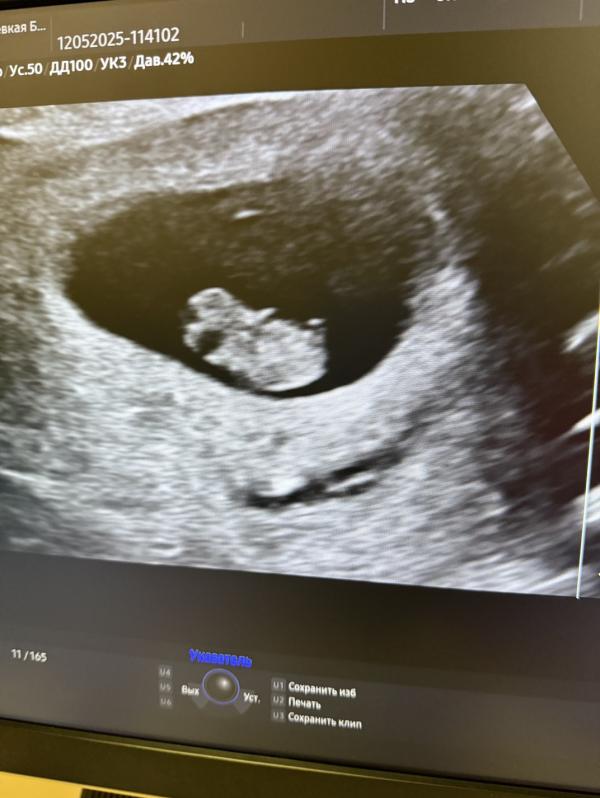

Гематома куда-то рассосалась сама! Я счастлива, 😊 что все в порядке, а думала, что в больницу положат, 🚐 но все обошлось. 😅😌 Я теперь успокоилась и буду спать спокойно, завтра пойду сдавать анализы и буду вставать на учет по беременности. По узи срок 8.1 🍒 Уже машет ручками нам 😍